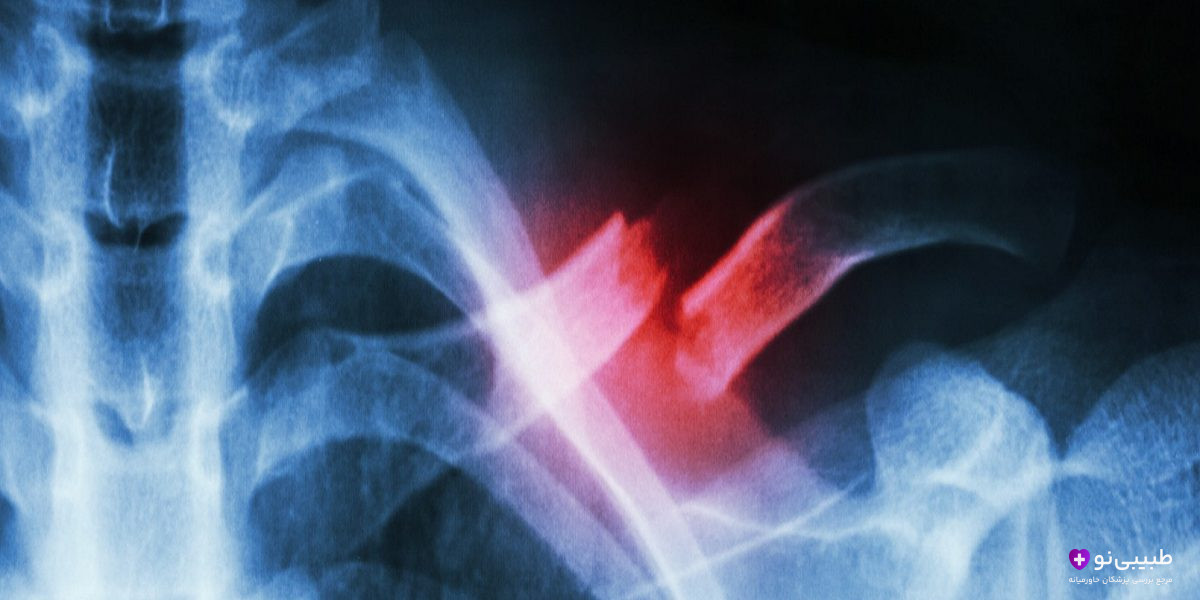

نشانههای نچسبیدن استخوان (Nununion)

اصطلاح پزشکی نچسبیدن استخوان وقتی استفاده میشود که دو سر استخوان شکسته به هم متصل نشود. علائم هشدار دهندهای که نشان از نچسبیدن استخوان دارند عبارتند از:

- درد مزمن و بعد از چندین هفته

- عدم توانایی در استفاده از اندام آسیب دیده به خصوص در حرکات ساده

- تورم پایدار و ایجاد التهابهای موضعی

در برخی موارد بیمار صدای تقتق یا جابهجایی استخوان را نیز حس میکند.